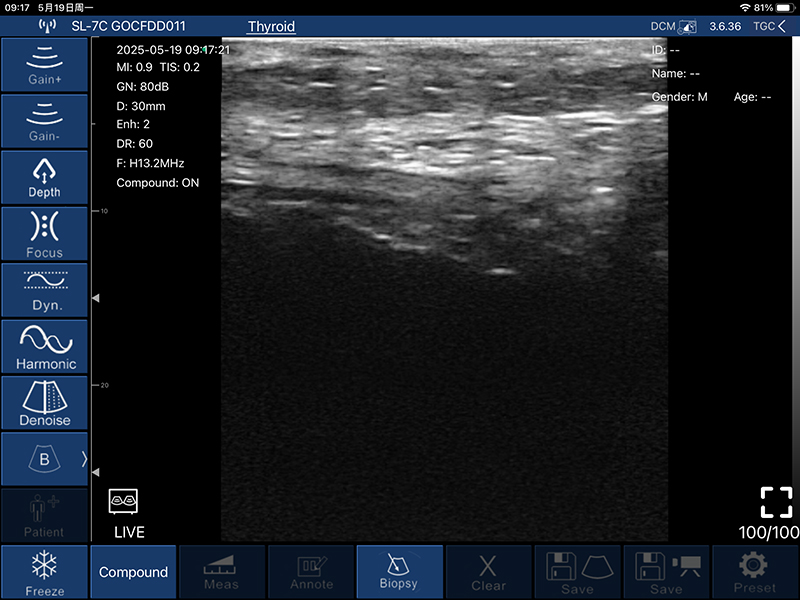

• B模式

增益:30db-105db

降噪:0-1-2-3-4

动态范围: 40-50-60-70-80-90-100-110

• 图像调节:增益、焦点、

反相脉冲谐波、降噪